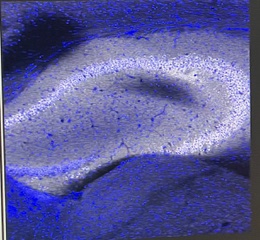

On Tuesday, I learned the final steps of the Click reaction process. This involved washing the tissue and staining it with a fluorescent dye called DAPI, which specifically targets the nucleus. This step allows us to visualize how the drug affects different neurons by comparing the fluorescence patterns of the drug (with a different dye) and the nucleus.

On Thursday, I began by mixing reaction buffer for the Wednesday tissue samples, initiating the final stages of the Click process. After the reaction, I cleaned the tissue with a solvent and stained the nucleus with DAPI for mounting on a slide. Finally, I excitedly took the slide to the imaging room with my mentor to see if the Click chemistry I performed independently was successful. To my relief, the slide showed clear patterns, allowing me to visualize the effects of the PF-04457845(PF) drug.